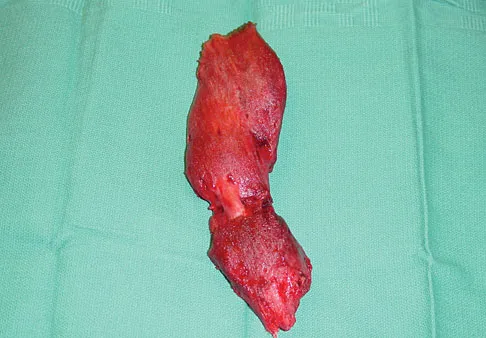

Question 56:

A 23-year-old man has had right posterolateral knee pain and occasional lateral calf dysesthesias for the past 8 months. A radiograph, CT scan, MRI scans, and a biopsy specimen are shown in Figures 62a through 62e. What is the most likely diagnosis?

Options:

- Osteoid osteoma

- Brodie's abscess

- Osteoblastoma

- Chondroblastoma

- Osteosarcoma

Correct Answer: Osteoid osteoma

Explanation: